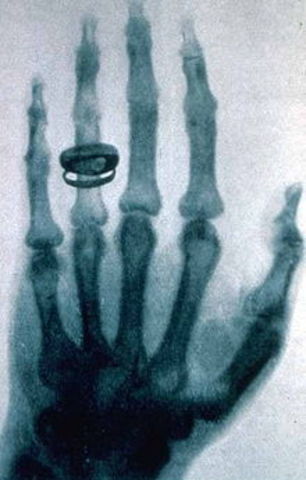

• Открытие рентгеновского излучения

Открытие рентгеновского излучения

Рентгеновское излучение было открыто Вильгельмом Конрадом Рентгеном. Изучая экспериментально катодные лучи, 8 ноября 1895 года он заметил, что находившийся вблизи катодно-лучевой трубки картон, покрытый платиносинеродистым барием, начинает светиться в тёмной комнате. В течение нескольких следующих недель он изучил все основные свойства вновь открытого излучения, названного им X-лучами. НиколаТесла же предположил опасность длительного воздействия рентгеновских лучей на человеческий организм.